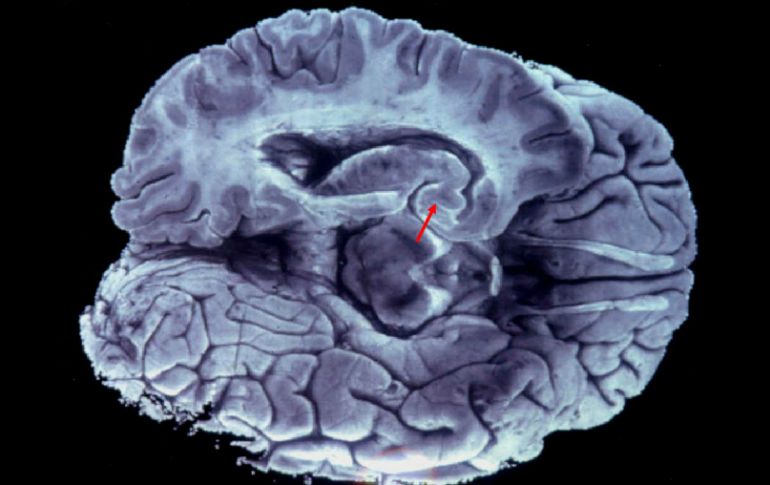

Suplementos | Destacan la importancia de mantener una alimentación adecuada Expertos llaman a prevenir enfermedades neurodegenerativas Destacan la importancia de mantener una alimentación adecuada Por: NTX 18 de octubre de 2015 - 12:54 hs Las células neuronales no se regeneran y esto se ha visto en el hipocampo. EFE / ARCHIVO CIUDAD DE MÉXICO (18/OCT/2015).- Con el avance de edad en la población y para evitar el incremento en las cifras de enfermedades como Alzheimer y el Parkinson es necesario tomar las medidas de salud necesarias para prevenirlas. Ante esta situación, en el Monumento a la Revolución se realizan este domingo distintas actividades en el evento "Alzheimer, aprende y actúa" para informar a la población sobre estos padecimientos. El neurocirujano José Figueroa Gutiérrez destacó la importancia de mantener una alimentación adecuada basada en productos naturales, y muy importante, reducida en carbohidratos además de agregar el uso de antioxidantes para evitar este padecimiento. En entrevista agregó que también es necesaria la actividad física y principalmente un estilo de vida que evite el estrés crónico ya que este es muy dañino para el cerebro y sus órganos. El investigador de la Facultad de Medicina de la UNAM abundó que también es necesario mantener activo al cerebro mediante prácticas que de preferencia brinden un beneficio adicional como aprender otro idioma, tocar un instrumento o incluso realizar crucigramas o leer. Manifestó que ya se ha demostrado y eliminado el mito de que las células neuronales no se regeneran y esto se ha visto en el hipocampo, región cerebral que si se activa en forma intensa se puede dar esta regeneración. Para esto el Banco Nacional de Cerebros del Centro de Investigación y de Estudios Avanzados (Cinvestav) en el que también colabora se realiza trabajo de investigación sobre el Alzheimer y tiene una muestra de cerebros tanto sanos como enfermos en este evento para que la gente conozca de manera física este padecimiento. La química farmacobióloga Berenice Dionisio, alumna de quien coordina este banco, José Luna, mostró en un corte cerebral las afectaciones por esta enfermedad en la que el tamaño del cerebro se encuentra disminuido así como el hipocampo, que es el encargado de los recursos a corto y largo plazo. Añadió que también las circunvalaciones del cerebro disminuyen debido a la muerte neuronal que se va relacionando con esta enfermedad. En el evento que concluirá este domingo los asistentes podrán encontrar talleres y pláticas así como obras de teatro e información sobre cómo tratar y cuidar a los pacientes. Temas Enfermedades Cerebro Alzheimer Calor de hogar Salud general Lee También Bajan lluvias el sábado en Guadalajara, pero se mantiene nublado La edad de riesgo de padecer un trastorno mental, según expertos ¿Cuál es la diferencia entre los celos y la enfermedad de celotipia? ¿Cuánto tarda una persona con depresión en llegar al tratamiento? Recibe las últimas noticias en tu e-mail Todo lo que necesitas saber para comenzar tu día Registrarse implica aceptar los Términos y Condiciones